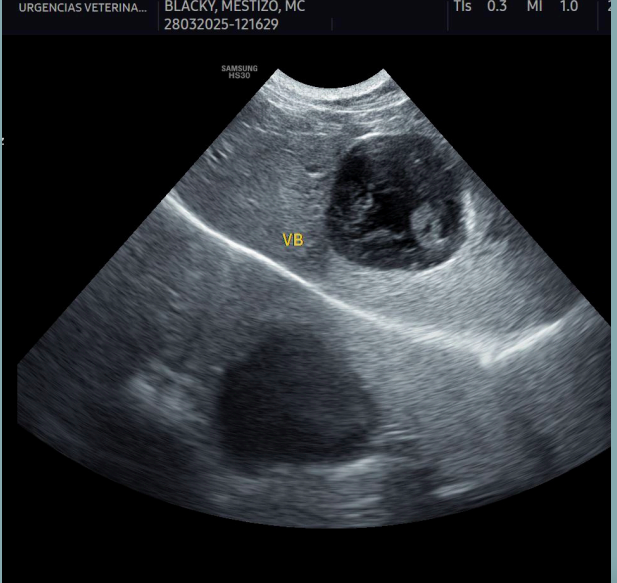

Artefactos: Sombra de borde

- Se forma en los bordes de estructuras curvas o redondeadas, como un quiste, un vaso sanguíneo o una lesión nodular.

- La imagen muestra una sombra longitudinal a cada lado del borde de la estructura redondeada, debido a la refracción de las ondas en el borde estructural.

Artefactos: Refuerzo posterior

- Las ondas sonoras pasan a través de un tejido de baja densidad (fluido) y presentan una mayor intensidad respecto a otras ondas en el mismo plano de profundidad.